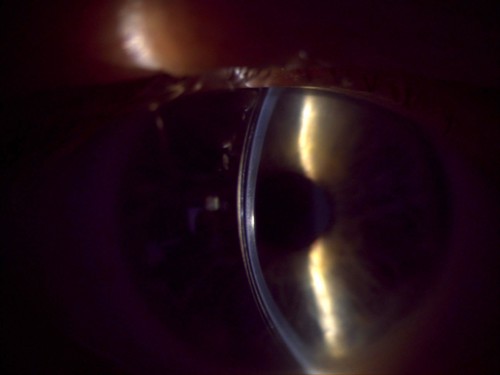

Upon conversing with the patient, we learned that he was seeking a lens option that provided similar optical quality to GPs with better stability, and he did not want to use reading glasses. After completing tomography scans and refraction, we determined that a scleral lens was the best option. The manifest refraction measured at -2.25 -5.25 @ 084 and 0.00 -1.75 @ 090 with a visual acuity of 20/40 OD and 20/30 OS with glare.

A scleral lens was applied to both eyes as a trial, and the patient noted immediate improvement in comfort and stability. Mild posterior tear film debris was caused by inferior lens decentration in both eyes. With the quadrant-specific haptics in the lens design, minor changes were instilled to improve comfort and fogging issues. We then completed an over-refraction and demonstrated a +1.50 for reading power, and the patient read J1.

At the original consultation, we chatted in depth about the potential for multifocal scleral lenses. The patient was informed about the potential limitations and adaptation of multifocal scleral lenses, and we decided to proceed. The choice for the multifocal design was a SmartFocus lens (BostonSight). We ordered the lenses after finalizing a stable fit and then dispensed the lenses.